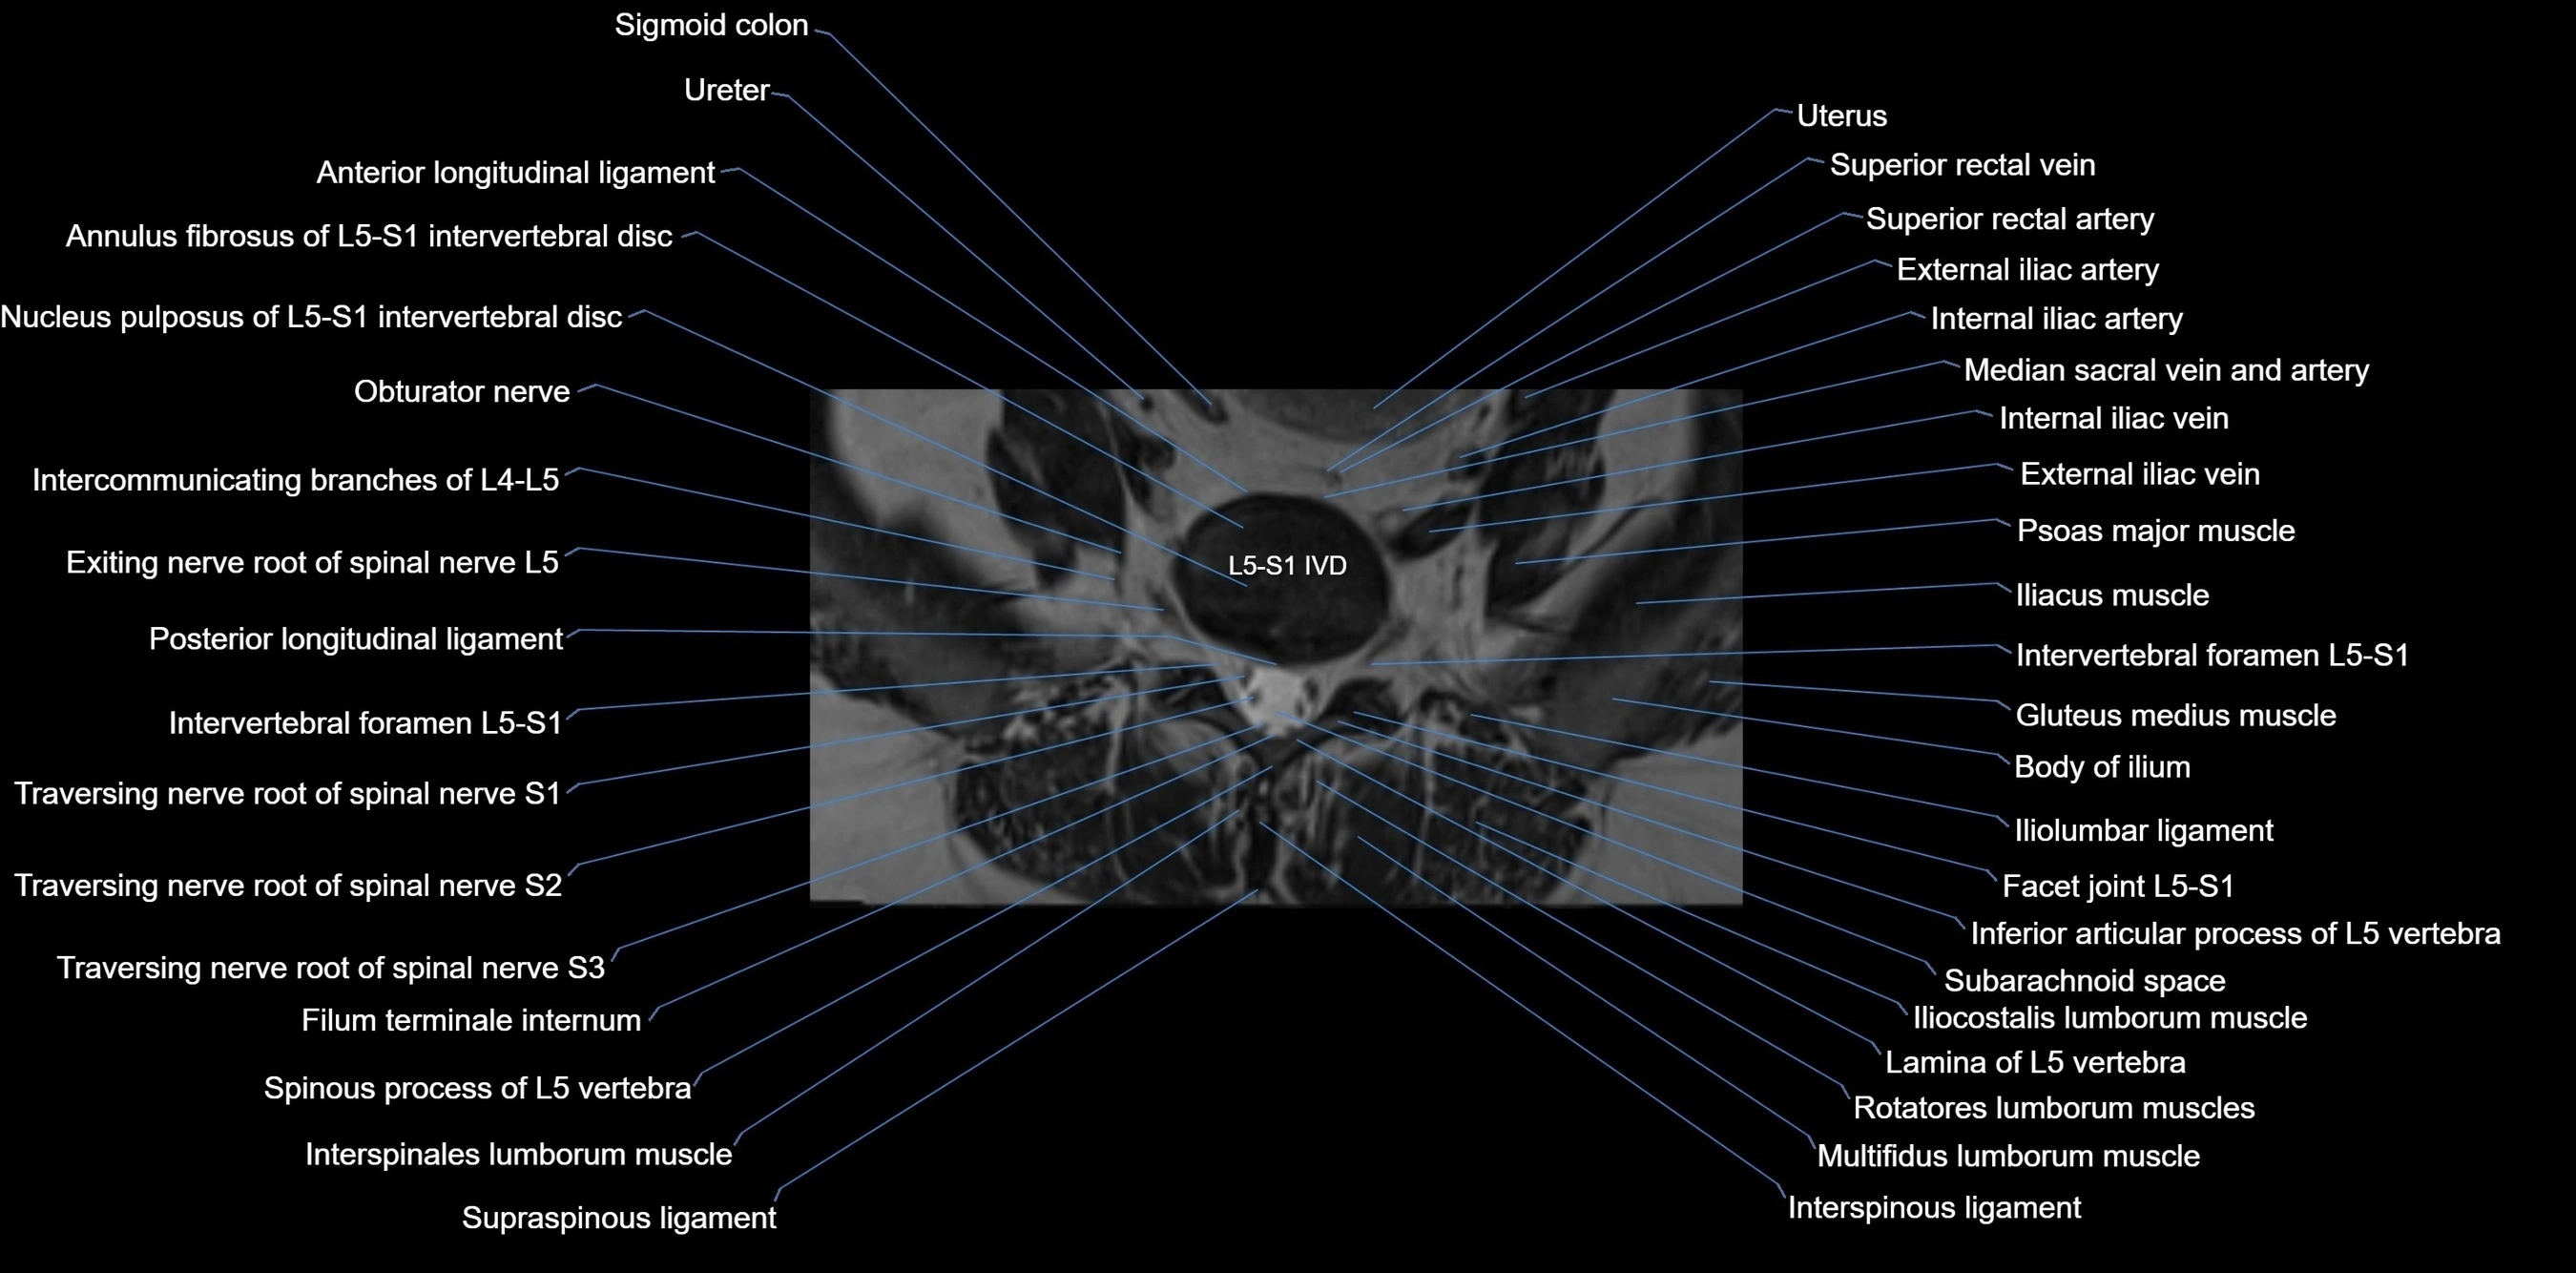

MRI image

image